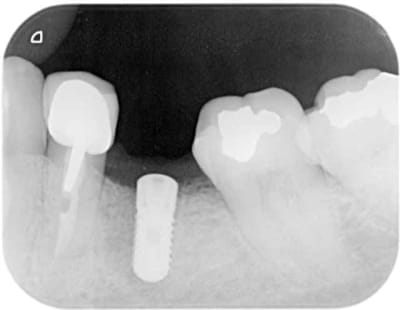

pour changer de sujet

un échec d'endo.

première consult en 3/2009 atteinte de 35

dépose de la ccm repirse d'endo repose de la ccm tenon raccourci

mais évolution+++ de la lésion qui m'a conduit à l'avulsion de la dent en septembre curetage soigneux et mise en place de : rien

en janvier pano de controle avec petit repère (tige maillefer recoupée à 10mm) dans du silicone

janvier pose d'un natéa en 4.1*10

pas de photo désolé

pour humator : non en fait si tu regardes endo paro en mesial

pour pxav : surface de contact os implant en 4.1*10 superieur a 12*3.3 et en plus le mentonnier fait sa boucle juste la c'est pour ça que pas plus long